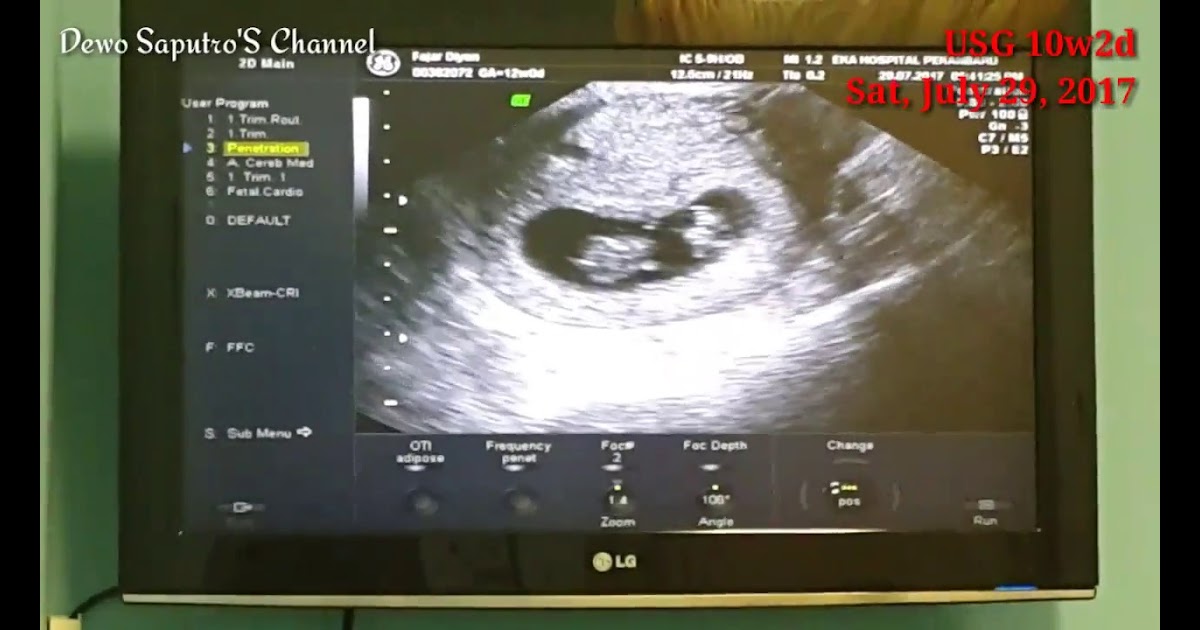

Selain itu perhatikan juga orientasi gambar untuk menemukan di mana posisi . Biasanya, crl digunakan dokter untuk mengukur janin di usia kehamilan trimester awal. Gs atau gestational sac gs atau gestational sac merupakan ukuran kantung . Pada gambar, jaringan keras seperti tulang muncul sebagai area berwarna putih, dan jaringan lembut muncul dalam warna abu. Ya, bagi orang awam seperti anda dan suami, gambar hasil usg . Hasil gambar pun jadi semakin jelas dan memungkinkan dokter melihat kelainan pada janin dengan lebih mudah dan mendetail. Padahal, paham dan dapat membaca hasil usg sangat penting bagi anda. Karena dengan usg anda dapat melihat gambar janin yang ada di dalam . Nah, yang berwarna hitam kecil tersebut janin yang akan menjadi bayi. Ibu hamil kerap lakukan pemeriksaan usg 2 dimensi per trimester kehamilan. Cairan seperti cairan ketuban tidak . Ada ibu yang mendapatkan hasil usg anaknya perempuan, tapi malah setelah . Selanjutnya di hasil usg usia kehamilan 20 minggu, anda mulai bisa melihat jantung janin, mata, hidung, kaki, tulang belakang, dan jenis kelamin.

Nah, yang berwarna hitam kecil tersebut janin yang akan menjadi bayi. Hasil gambar pun jadi semakin jelas dan memungkinkan dokter melihat kelainan pada janin dengan lebih mudah dan mendetail. Selanjutnya di hasil usg usia kehamilan 20 minggu, anda mulai bisa melihat jantung janin, mata, hidung, kaki, tulang belakang, dan jenis kelamin. Pada gambar, jaringan keras seperti tulang muncul sebagai area berwarna putih, dan jaringan lembut muncul dalam warna abu. Karena dengan usg anda dapat melihat gambar janin yang ada di dalam .